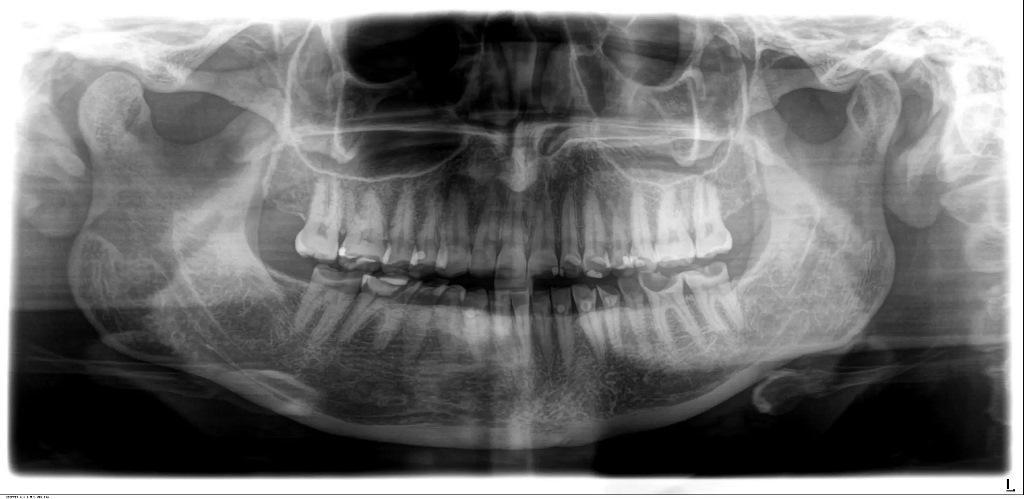

Клиническое и рентгенологическое обследование выявило выраженные эрозивные дефекты на всех зубах (фото 1a-f). Чтобы предотвратить ночное изнашивание оставшимся структурам зубов, стоматолог общей практики ранее изготовил пациентке окклюзионную шину (каппу). Был проведен экспресс-скрининг на височно-нижнечелюстные расстройства с использованием инструмента, разработанного Немецким обществом краниомандибулярных функций и расстройств, который не выявил никаких функциональных отклонений. Был определен общий диагноз: сильно выраженная эрозия из-за воздействия экзогенной кислоты (кола), истирание с уменьшением OVD, множественные кариозные поражения, гиперчувствительность дентина, гингивит и нарушение эстетики.

Фото 1f: Панорамная томограмма.